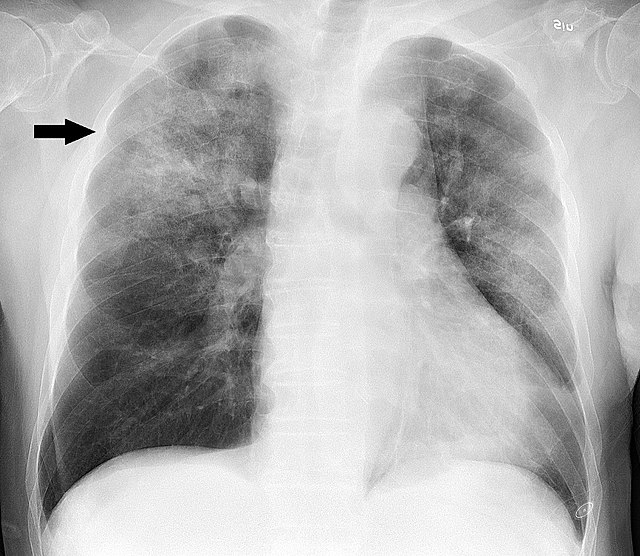

급성폐렴으로 확인되는 흉부 X레이 사진 <화살표> 발열과 기침, 간과하기 쉬운 초기 증상

급성폐렴은 대부분 발열, 마른기침 혹은 가래 동반 기침이 나타나지만, 초기 단계에서 이를 단순 감기로 오인하는 경우가 많습니다. 이 시기를 놓치면 증상이 빠르게 진행되어 폐렴이 심화될 수 있으므로, 38도 이상의 고열이 수일간 지속되거나 호흡이 가빠지는 느낌이 있다면 즉시 전문의와 상의하는 것이 중요합니다. 가족 중 면역력이 취약한 어르신 혹은 어린이가 있다면, 집안 공기 질 관리와 개인위생을 더욱 철저히 해주는 것이 중요한 숨겨진 핵심 팁입니다.